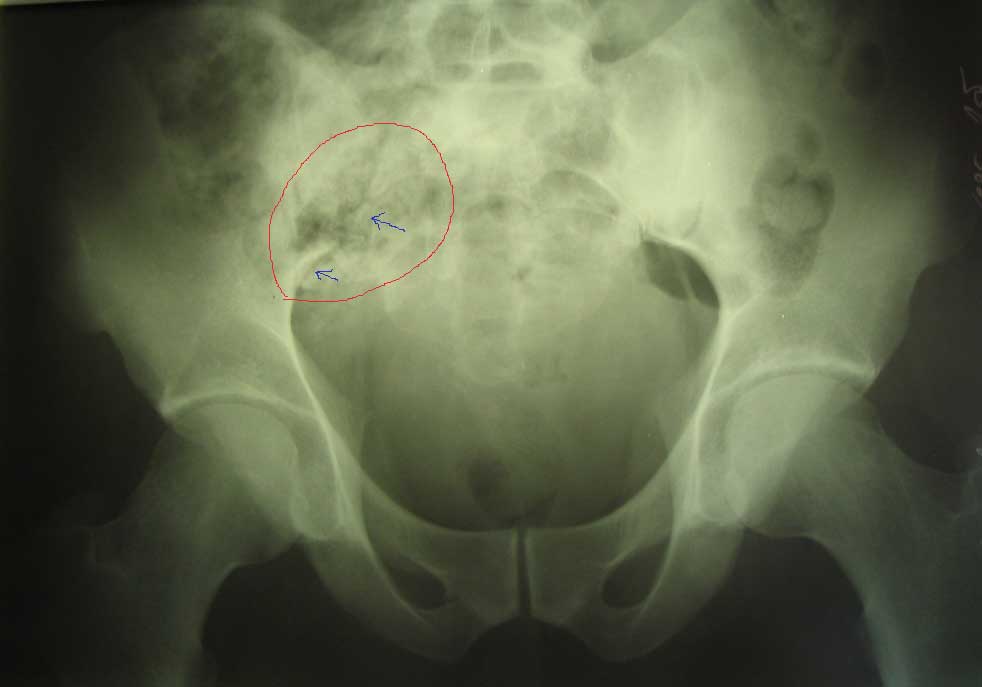

живот |  крестец |  плечо |  спина |  снимок |  снимок-схема | Поработал, блин... Шмальнули в него из"калаша" почти в упор: сквозное ранение живота с повреждением подвздошной кишки (вход -правая подвздошная область, выход на крестце), касательное левого плеча (пуля прошла подкожей) и практически царапина на правом плече.Ранение - 6.03, в этот же день прооперирован - ушивание ран подвздошной кишки и т.н."обработка" раны левого плеча (зачем-то удалили отслоенный мостик кожи... :-/ ). Черездень - релапаротомия, резекция участка подвздошной кишки. До России он добрался только25.03 (КАК он добрался - отдельная история...), с хорошо гноящимися и разошедшимися ранамина передней брюшной стенке, крестце и левом плече (см. фото в аттаче). В принципе с ранамивсе понятно, санация-заживление-пластика... И это не самое страшное... Сегодня выполнена рентгенография - оскольчатый перелом крестцово-подвздошного сочленениясправа. Плюс к этому - выраженный парез правой н/конечности с выпадением чувствительностии парестезиями (хотя частично чувствительность сохранена, и какое-то подобие произвольныхдвижений тоже есть). Поэтому хотелось бы спросить - какова должна быть тактика в отношенииперелома (режим, лекарства и т.п.) и в отношении неврологии? Также интересуют возможныеисходы... Приветствуются все мысли, замечания и предложения... -- С уважением, Андрей Башлачев mailto:bashlachev@yandex.ru Ивановская государственная медицинская академия, кафедра хир. болезней пед. ф-та

АБ> Сегодня выполнена рентгенография - оскольчатый перелом

АБ> подвздошно-бедренного сочленения

опечатался, крестцово-подвздошного...

Учитывая, что основная часть сустава цела, хирургическая стабилизация не требуется. Там, видимо, перестрелены корешки. Медикаменты тут никакие не помогут, разве что если будут каузалгии, тогда добавить финлепсин или амитриптилин. А все-таки какие поточнее неврологические выпадения? Стопа висит? Надо посоветоваться с нейрохирургами по поводу целесообразности ревизии.

Сегодня консультирован зав. отд. гнойной травматологии и зав. отд. спинальной нейрохирургии. Пришли к выводу, что в первую очередь необходимо заниматься крестцом (профилактировать остеомиелит, дообследовать, возможно - фиксировать тазовое кольцо), для чего больного нужно переводить в травму. Что касается неврологических проявлений - это все вторично (из-за контузии - отека - и т.п.).

в отношении перелома. Интересно посмотреть проекции "inlet","out let" возможно они помогут определиться в отношении тактики лечения повреждения таза.